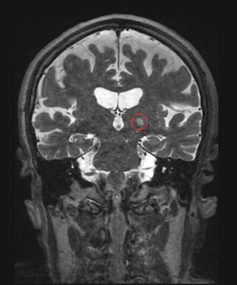

MRI of a patient treated for essential tremor using focused ultrasound, with the targeted part of the brain circled in red.

Jmarchn/Wikimedia Commons, CC BY-SA

It is only after scientists made key advances in imaging technology and acoustic physics in recent years that the promise of ultrasound is being realized in the clinic. Hundreds of clinical trials aimed at treating dozens of conditions have been completed or are ongoing. Researchers have found notable success on a condition called essential tremor, which leads to uncontrolled shaking, usually of the hands. Focused ultrasound treatments for essential tremor are now performed routinely at many locations around the world.